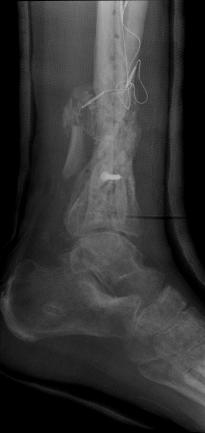

Pre-corrective surgery X-Rays of the damaged right & left legs / ankles

These x-rays were taken at Dr Armendariz’s office, just prior to performing any corrective surgery. As can be seen in these images,

there was no tibia bracing provided by Dr. Keller. Liam was released from Dr Keller’s care with instructions that full weight bearing could

be accomplished within 2 months of Keller’s last surgical procedure. The best example to examine is the second image (from the left) of the

top how. Notice how the bones that should be aligned with the tibia are in fact on the other side of the leg. The third image shows how badly

Liam’s left foot was twisted as a result of the pool placement of the external fixation. What is not obvious is that the screw at the bottom

of the plate on the right fibula missed being screwed into the plate.